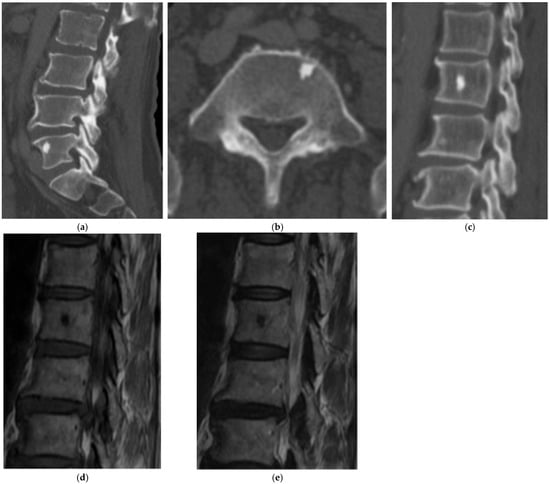

2.1.1. Axial Enostosis (Bone Island)

- Sala, F.; Dapoto, A.; Morzenti, C.; Firetto, M.C.; Valle, C.; Tomasoni, A.; Sironi, S. Bone Islands Incidentally Detected on Computed Tomography: Frequency of Enostosis and Differentiation from Untreated Osteoblastic Metastases Based on CT Attenuation Value. Br. J. Radiol. 2019, 92, 20190249. [Google Scholar] [CrossRef]

- Onitsuka, H. Roentgenologic Aspects of Bone Islands. Radiology 1977, 123, 607–612. [Google Scholar] [CrossRef]

- Greenspan, A. Bone Island (Enostosis): Current Concept—A Review. Skelet. Radiol. 1995, 24, 111–115. [Google Scholar] [CrossRef]

- Luo, H.; Zou, L.; Yang, Q.; Yuan, C.; Ma, K.; Yang, S.; Luo, D.; Liu, C.; Liu, Z. Spectral CT Assists Differentiation of Osteoblastic Bone Metastasis from Bone Island in Newly Diagnosed Cancer Patients. Eur. Radiol. 2024, 34, 60–68. [Google Scholar] [CrossRef]